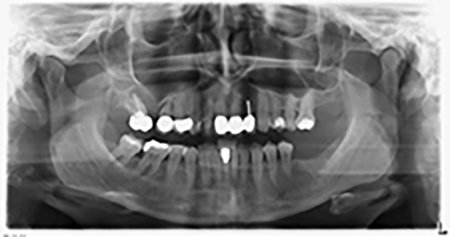

About six months after teeth 16 and 14 were extracted, a digital volume tomography (DVT, Planmeca) examination was performed for planning and risk minimization purposes. It clearly showed that the bone had not regenerated to the desired volume (Fig. 2 to 7).

To restrict the augmentation to region 14, and in consultation with the patient, it was planned that implant 16 would be placed, inclined, in the dorso-cranial direction (Fig. 8).

Sky implants supplied by bredent were implanted – tooth 16: 5.5 x 10mm and tooth 14: 4.0 x 10 mm.